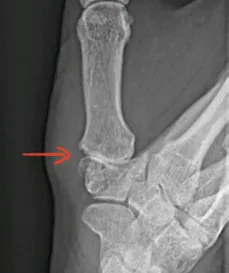

Thumb CMC arthroplasty can restore natural hand function but only if the trapezium cupis precisely placed

A misalignment of just 2° can weaken grip strengthand compromise long-term success

Surgeons rely on C-arm X-ray to guide CMC joint replacement but achieving the required level of accuracy is still dependent on extensive training and individual skill.